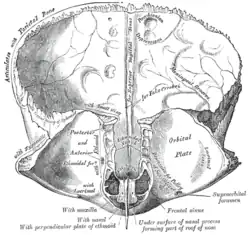

Frontal bone. Inner surface. (Frontal crest visible at center but not labeled.) | |

The frontal crest is a ridge on the internal surface of the squamous part of the frontal bone formed by the inferior convergence of the two edges of the sagittal sulcus. The frontal crest gives attachment to the falx cerebri.[1]